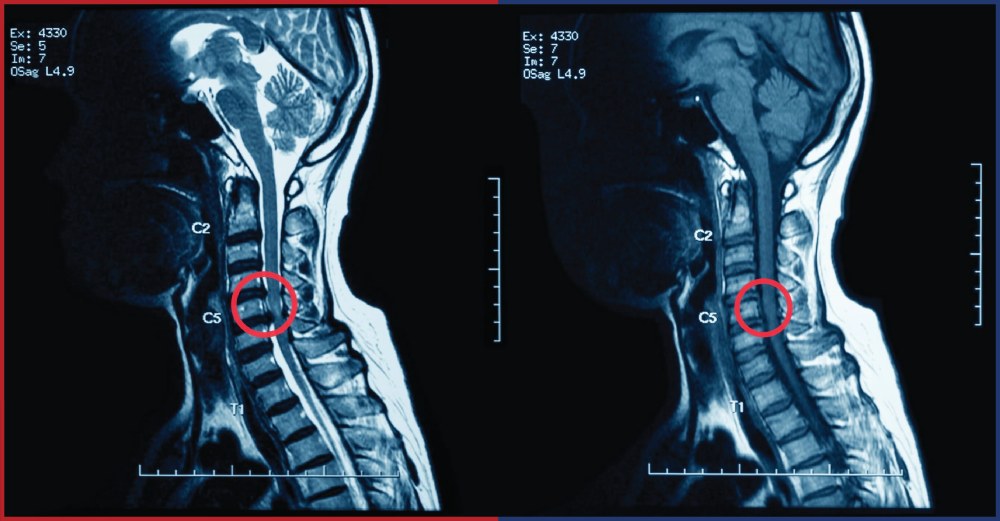

การวินิจฉัยโรค

การวินิจฉัยโรคหมอนรองกระดูกคอกดทับเส้นประสาทเป็นขั้นตอนที่สำคัญในการกำหนดแนวทางการรักษาที่เหมาะสม แพทย์จะสอบถามประวัติทางการแพทย์และอาการของผู้ป่วย รวมถึงการตรวจร่างกายเพื่อประเมินสภาพของกระดูกสันหลังและเส้นประสาทด้วยการตรวจ